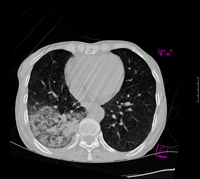

标题: CT9563:女67岁,咳嗽咯白痰伴纳差一月。右肺呼吸音低可闻及 [打印本页]

女67岁,咳嗽咯白痰伴纳差一月。右肺呼吸音低可闻及湿罗音。白细胞及淋巴细胞不高,无发烧

1、右上胸廓塌陷,纵隔气管右移

2、病灶靠后方,一般结核多见一点

3、病灶内,纵隔内有少许钙化灶

3楼的肺细支气管肺泡癌也不能完全排除,毕竟患者年纪大,病史短,临床上感染症状不明显,建议短期内复查吧

病灶范围较大,病史较短,病人年龄较大,结核中毒症状不明显, 考虑1右肺细支气管肺泡癌,2.硬化性淋巴瘤,建议进一步检查